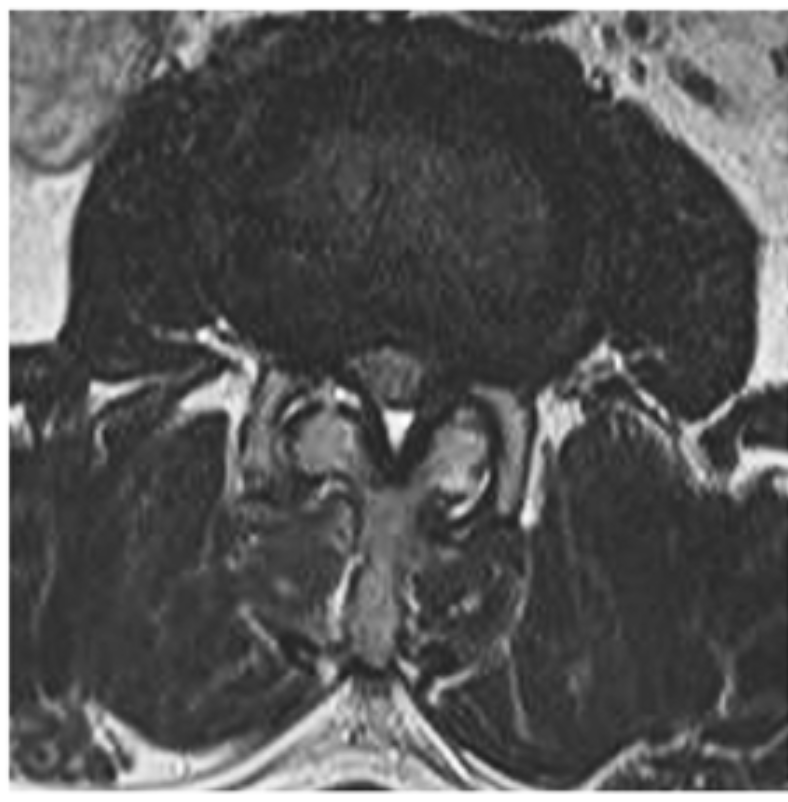

Slide the arrows to see what endoscopic spine surgery can do for your patient (L2-L3 Interlaminar Endoscopic Decompression)